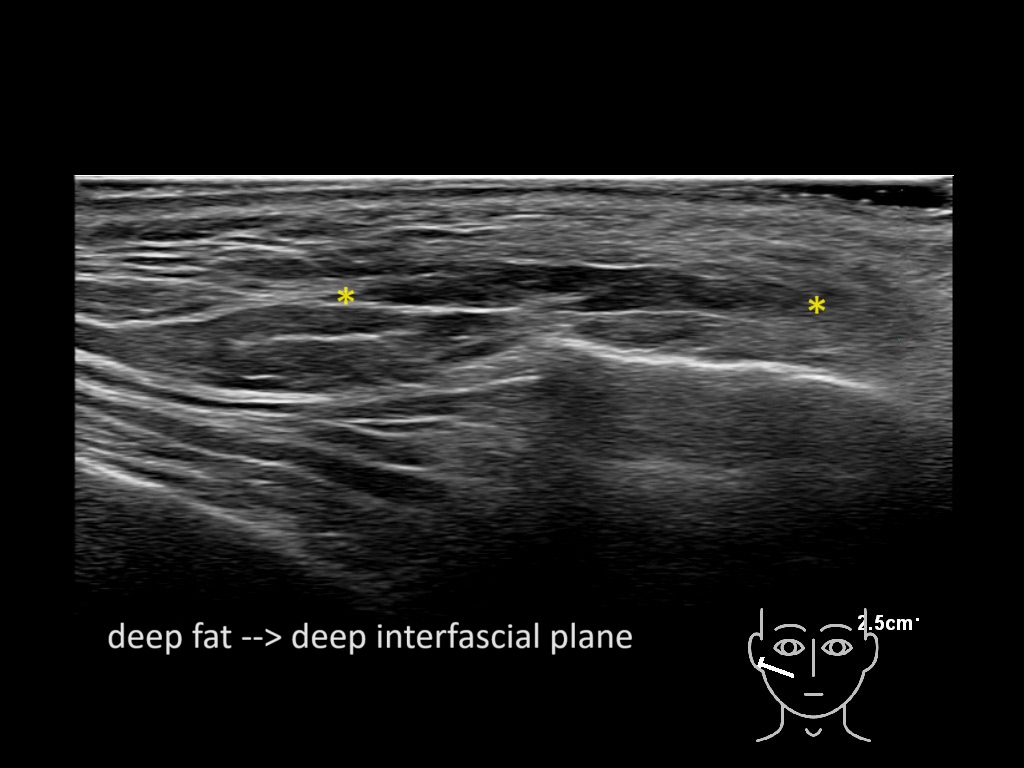

Filler behavior - Temple zygoma US

Study the first image to recognize the different layers. If you are sure about the layers, swipe to the second image to view the answer (if applicable).